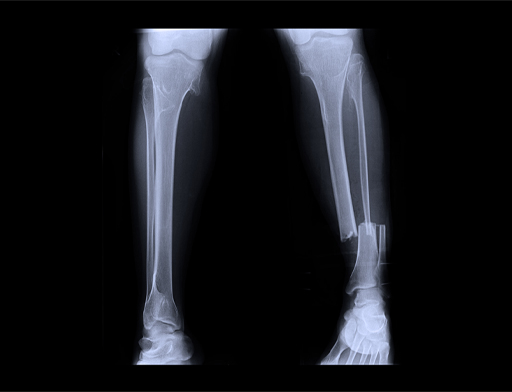

In the cases of Bobby Clay and Anna Boniface we see that they sustained low fuelling and overtraining for a period of time before experiencing bone fractures. This is partly because the body has stores of fat and glycogen for fuel, and it can break down stored fat and muscle protein to produce additional energy if needed. However, it can only survive in this state for a short time before the body is seriously affected and its systems, particularly the muscular and skeletal systems, become so damaged that they are no longer able to function effectively. This is when injuries start to occur.